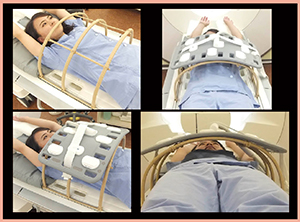

RVS用MRIは,超音波検査の体位に近い両上肢挙上でポジショニングし,体幹部コイルを用いて撮像を行っている。コイルの重みで乳房が潰れてしまうと適切にフュージョンが行えないため,コイルはタオルなどを用いて体表から浮かせて配置する必要がある(図1)。コイルを体表から浮かせるための補助具を作成してもよい(図2)。

図2 補助具を用いた場合のコイルセッティング |